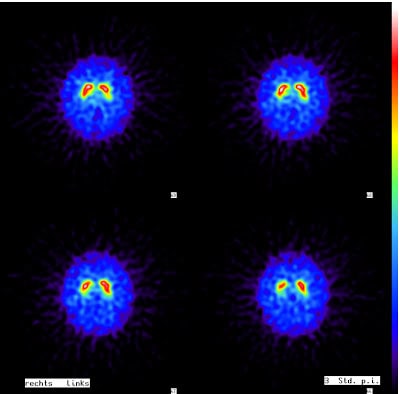

Parkinson-Erkrankungen und Parkinson-Syndrome (z.B. eine Multisystematrophie, MSA) können sehr empfindlich mittels eines DaTScans nachgewiesen werden.

Drei bis sechs Stunden nach Injektion einer schwach radioaktiven Untersuchungssubstanz werden Bilder angefertigt, die in der Regel direkt eindeutige Aussagen liefern.

Besteht anschließend noch Unklarheit, ob ein M. Parkinson oder ein Parkinson-Syndrom vorliegt, so ist die Unterscheidung mittels MIBG-Szintigraphie möglich, weil der M. Parkinson zu einer verminderten MIBG-Darstellung des Herzens führt.

Mittels DaTScan kann auch eine Levy-Body-Demenz (DLB) nachgewiesen werden, eine Parkinson-verwandte Erkrankung, bei der die geistigen Beeinträchtigungen noch vor den motorischen Störungen auftreten. Andere Demenzformen, wie die Demenz vom Alzheimer-Typ und die frontotemporale Lobärdegeneration (M. Pick), lassen sich bereits im Stadium des Mild Cognitive Impairments (MCI) erkennen. Die hierbei vorhandenen leichten kognitiven Störungen äußern sich durch Gedächtnisstörungen, Lernschwierigkeiten, Konzentrationsstörungen und schnelle geistige Ermüdung. Mittels Hirnperfusionsszintigraphie lassen sich bei den betroffenen Personen mit Alzheimer oder Pick-Demenz typische Durchblutungsstörungen nachweisen.